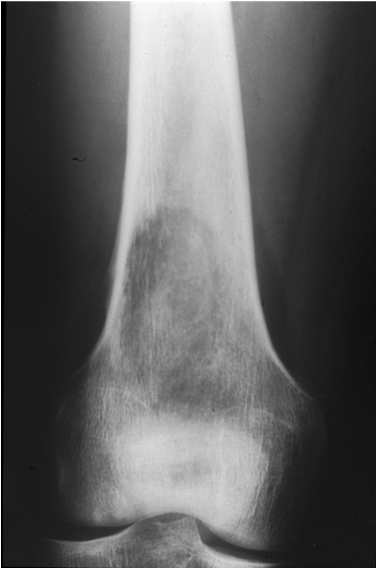

Fig. 11. Growth plate fracture with involvement of metaphysis and epiphyis (Salter-Harris type IV.